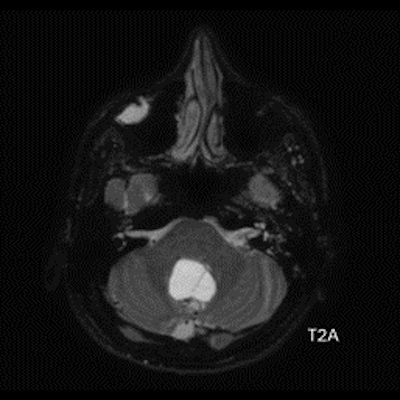

- B) Beyin MRG incelemesinde; 4. ventriküle bası etkisi oluşturan yaklaşık 3.5 cm boyutta, T2A hiperintens T1A hipointens kistik komponent (oklar) ve posteriorunda T1 ve T2A serilerde parankim ile izointens, içerisinde flow void alanların (oklar) izlendiği, post kontrast görüntülerde yoğun kontrast tutulumu gösteren mural nodül (oklar) barındıran düzgün sınırlı lezyon izlenmektedir.

- Kistik komponent: T1A hipointens, T2A hiperintens

- Mural nodül: T1A izo-hipointens, T2A orta derecede hiperintens olabilir.

- T1 ve T2A görüntülerde flow voidler sıktır.